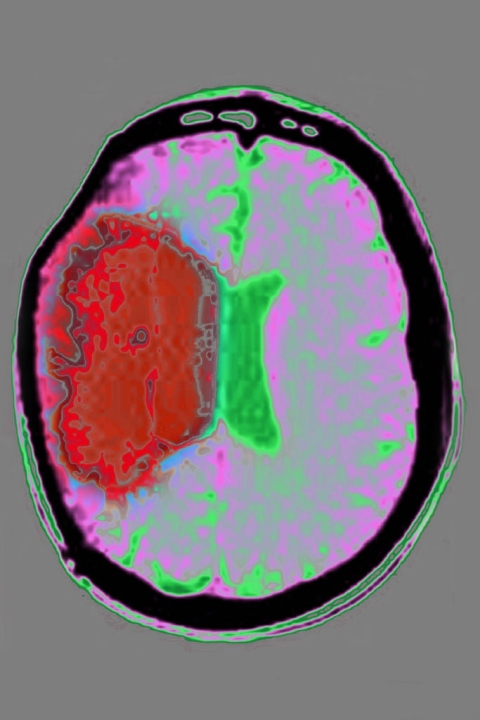

Эти планы основаны на вторых промежуточных результатах исследования фазы IIa BIRCH (NCT05970224), представленных Bioxodes в сентябре 2025 года. Исследование показало, что рекомбинантный белок имел тенденцию к замедлению расширения перигематомной отечности в течение десяти дней после инсульта. Пациенты, получавшие BIOX-101, также продемонстрировали уменьшение объема кровоизлияния через десять дней. Соотношение нейтрофилов и лимфоцитов показало благоприятные тенденции по сравнению со стандартным лечением, которое в настоящее время основано на хирургическом вмешательстве и применении антигипертензивных средств.

Признаки восстановления, наблюдаемые в когорте BIOX-101, также казались более благоприятными, чем у пациентов, получавших стандартное лечение: большее число пациентов в первой группе восстановили функциональную независимость к 90-му дню. Это измерялось по модифицированной шкале Рэнкина (mRS) с оценкой от 0 до 2. В исследовании приняли участие 23 пациента в десяти учреждениях Бельгии.